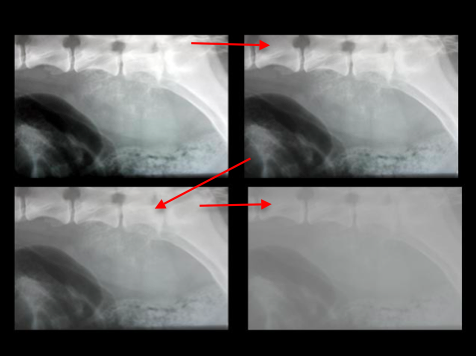

Forklar billedet

Jo højere kV man giver (energi/kvalitet af stråling) jo mere går igennem vævet og derfor falder den røde kurve. (Højt tal på anden aksen betyder meget absorberes). Der vil altså være mere “sort” (røntgenopklaring) på røntgen billedet. Compton photonerne afhænger ikke af kV og er samme niveau ved alle energiniveauer.

Hvad øges hvis man her følger pilene?

kV øges